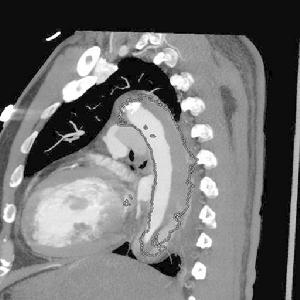

主動脈夾層動脈瘤(二)X線 胸部平片見上縱隔或主動脈弓影增大,主動脈外形不規則,有局部隆起。如見主動脈內膜鈣化影,可準確測量主動脈壁的厚度。正常在2~3mm,增到10mm時則提示夾層分離可能性,若超過10mm則可肯定為本病。主動脈造影可以顯示裂口的部位,明確分支和主動脈瓣受累情況,估測主動脈瓣關閉不全的嚴重程度。缺點是它屬於有創性檢查,術中有一定危險性。CT可顯示病變的主動脈擴張。發現主動脈內膜鈣化優於X線平片,如果鈣化內膜向中央移位則提示主動脈夾層,如向外圍移位提示單純主動脈瘤。此外CT還可顯示由於主動脈內膜撕裂所致內膜瓣,此瓣將主動脈夾層分為真腔和假腔。CT對降主動脈夾層分離準確性高,主動脈升、弓段由於動脈扭曲,可產生假陽性或假陰性。但CT對確定裂口部位及主動脈分支血管的情況有困難,且不能估測主動脈瓣關閉不全的存在。

(四)磁共振成像(MRI) MRI能直接顯示主動脈夾層的真假腔,清楚顯示內膜撕裂的位置和剝離的內膜片或血栓。能確定夾層的範圍和分型,以及與主動脈分支的關係。但其不足是費用高,不能直接檢測主動脈瓣關閉不全,不能用於裝有起搏器和帶有人工關節、鋼針等金屬物的病人。

(五)數字減影血管造影(DSA) 無創傷性DSA對B型主動脈夾層分離的診斷較準確,可發現夾層的位置及範圍,有時還可見撕裂的內膜片,但對A型病變診斷價值較小。DSA還能顯示主動脈的血流動力學和主要分支的灌注情況。易於發現血管造影不能檢測到的鈣化。